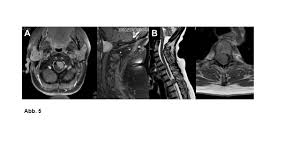

Universitatsklinikum Des Saarlandes Fallbeispiele